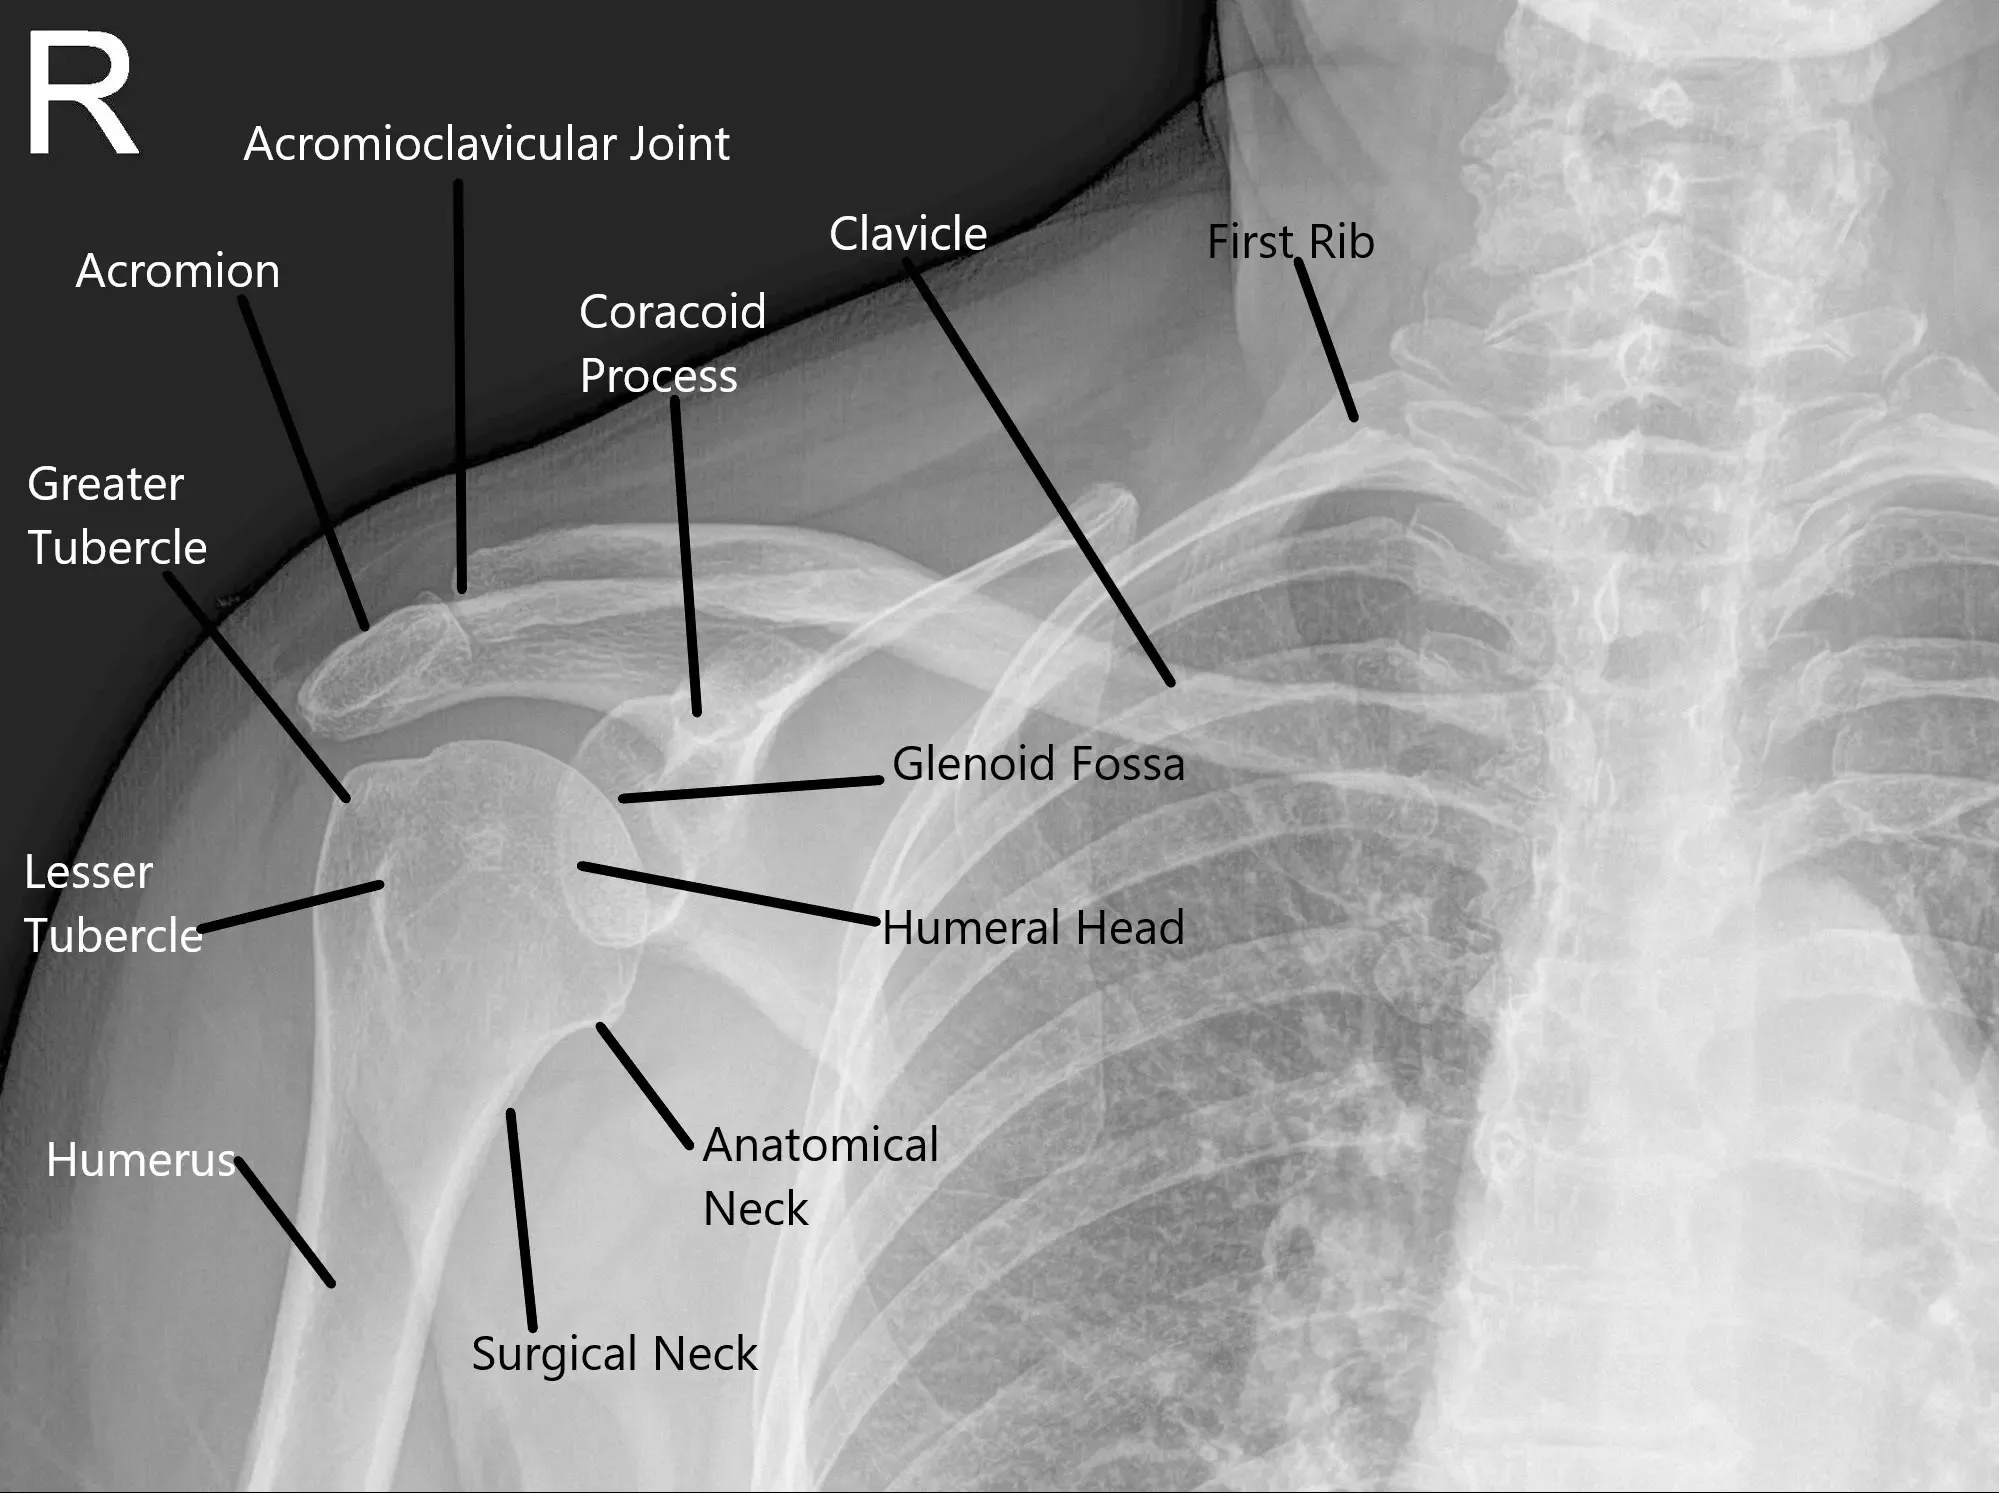

X-ray of the shoulder joint in the AP view.

The diagnosis of snapping scapula syndrome is made based on a thorough physical examination and medical history. Physicians will often ask about the patient’s activity levels and any history of trauma or repetitive shoulder movements. Imaging techniques, such as X-rays, CT scans, and MRI, are used to evaluate bone structure, detect fractures, and assess soft tissues like muscles, tendons, and bursae. X-rays may reveal bone malformations, while CT scans and MRIs provide more detailed images of the shoulder structures.